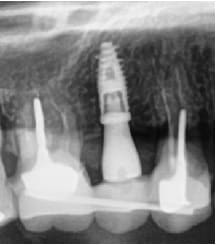

J'ai posé mercredi dernier un implant pour remplacer une 15 absente depuis des années sur un patient de 40 ans en bonne santé mais fumeur avec une parodontite chronique généralisée modérée stabilisée.

La crête étant pas mal résorbée en vestibulaire, j'ai opté pour la pose d'un implant de 3.6mm de diamètre ( biotech kontact 3.6/10) en faisant une expansion à l'aide d'ostéotomes.

Tous s'est à mon avis bien passé, j'ai passé mon foret pilote puis le 2mm jusqu'à la longueur désirée. Les forets suivants ont uniquement servi à franchir la corticale alors que la préparation du site était faite à l'aide d'ostéotomes de diamètres successifs jusqu'à 3.2mm. L'implant a ensuite été inséré dans l'axe que je voulais avec un couple final entre 30 et 50N/cm (en position légèrement sous-crestale). Puis rebasage du bridge provisoire.

La PM1 tire en effet un peu la gueule mais asymptomatique cliniquement + aucune image apicale au cbct. Aucune mobilité bien entendu. Je l'estimais conservable pour l'instant en unitaire mais trop risquée pour servir à nouveau de pilier de bridge...Et si on regarde de près, la 6 et la 7 tirent aussi "un peu" la gueule.

A l'examen clinique, il a un bel œdème au niveau de la joue mais rien de particulier au niveau du site opératoire. L'implant sonne bien mat et la percussion ne provoque aucune douleur. Palpation sensible en vestibulaire et en palatin, ce qui ne me parait pas extraordinaire à 5j post-op. RAS à la radio